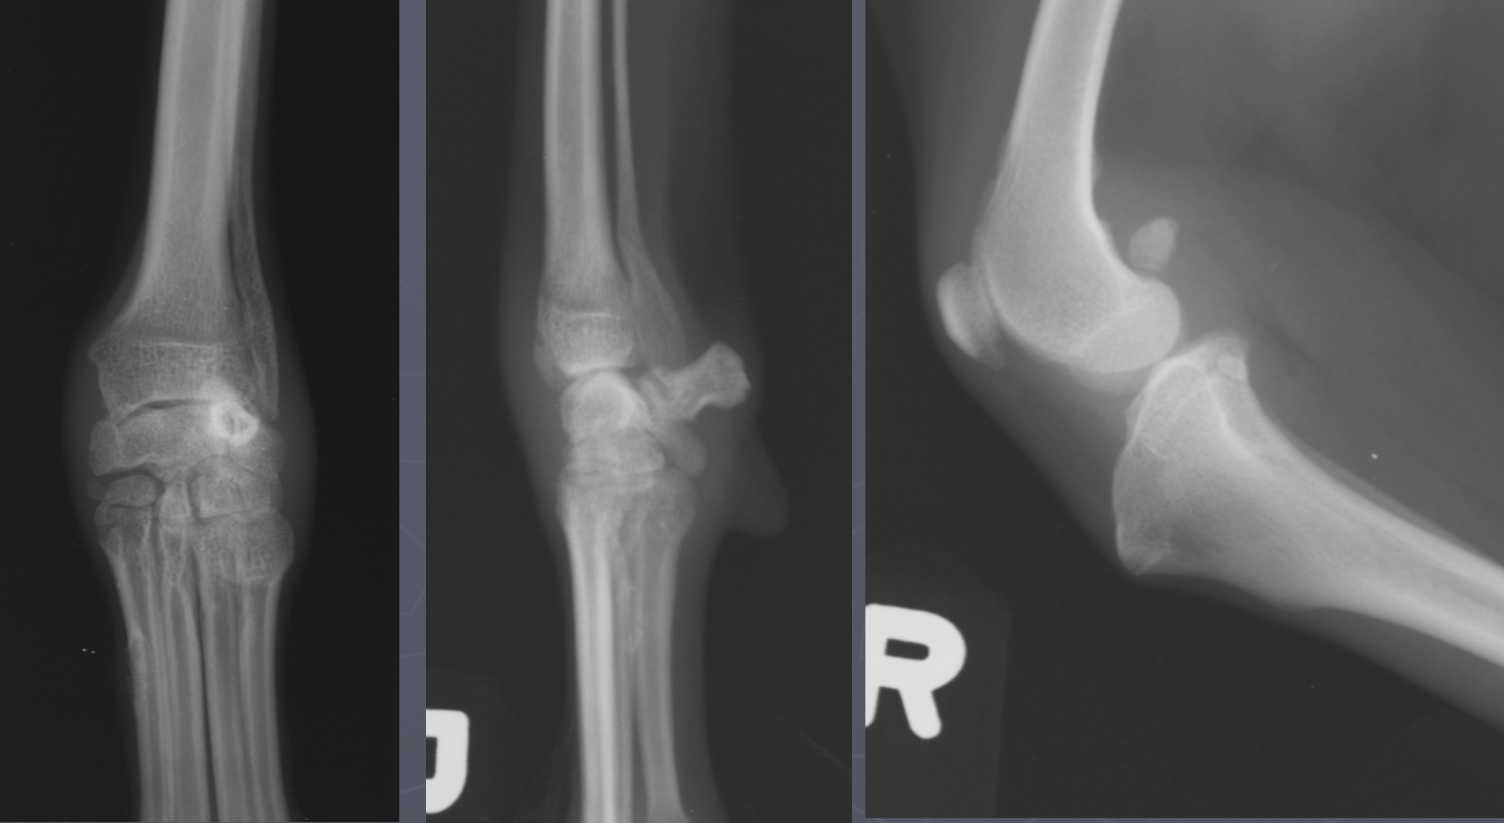

4 OCD lesion locations in the dog

cd humerus

medial humeral condyle (elbow)

lateral femoral condyle (knee)

medial trochlear ridge (ankle) - worst prognosis

which OCD lesions are these in the dog

A = cd humerus

B = medial humeral condyle (elbow)

C = medial trochlear ridge (ankle)

D =lateral femoral condyle (knee)

Dog OCD signalment

young giant breed (6-9 mo age)